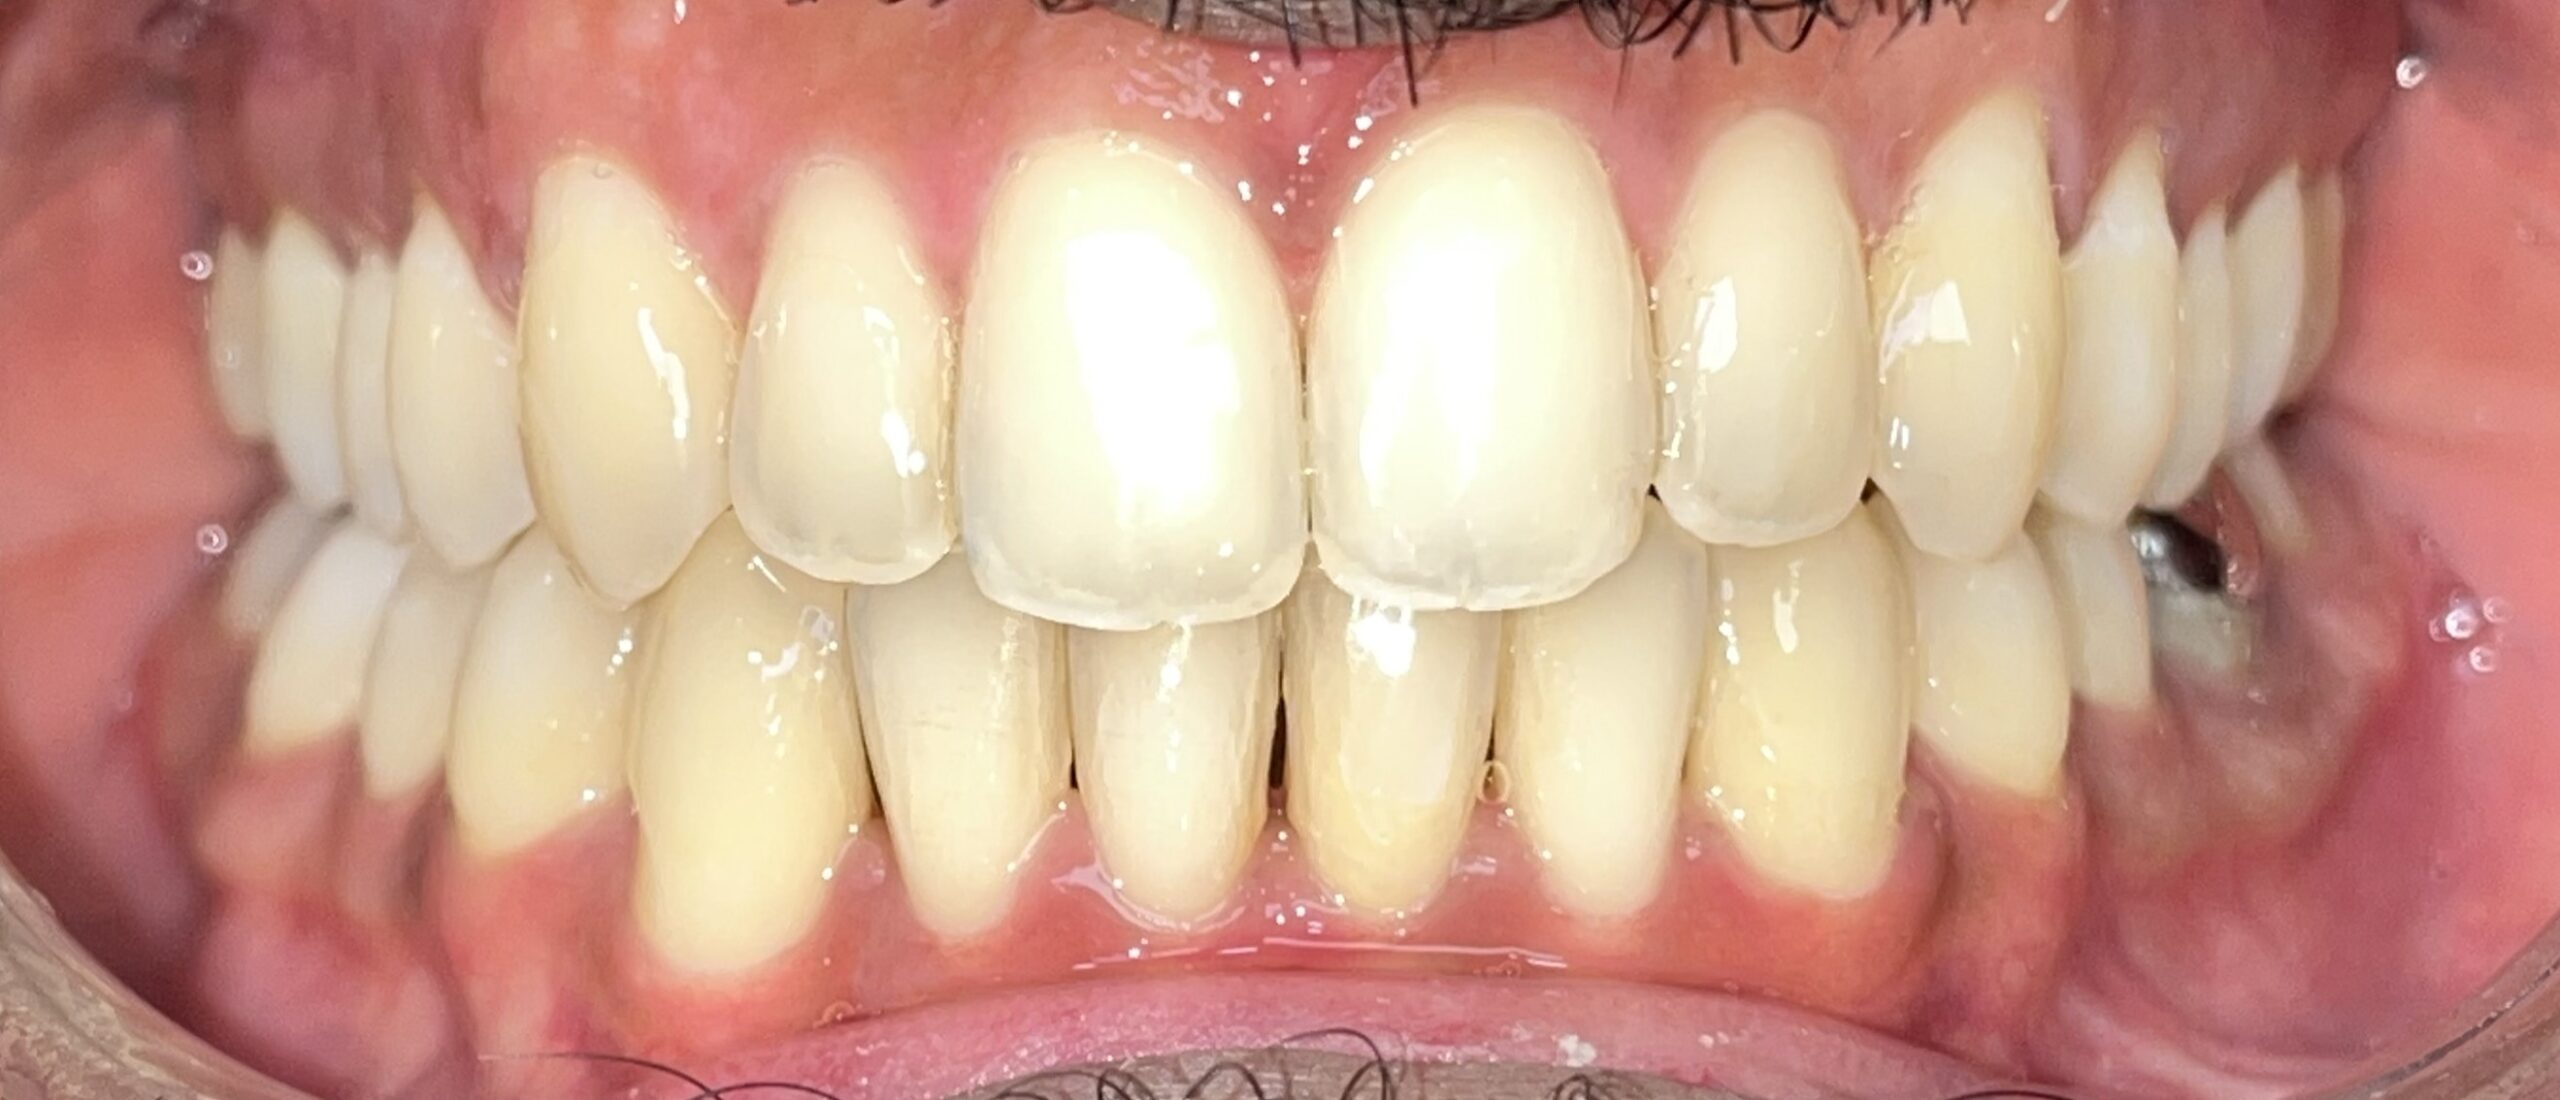

Before

After